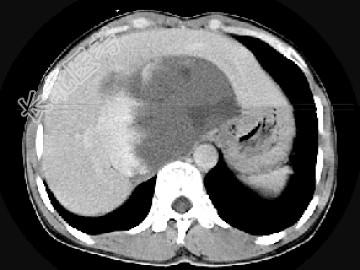

- 单项选择题女,48岁, 中上腹不适,CT扫描如图, 最可能的诊断为 ( )

A、原发性肝癌

B、胆管细胞癌

C、肝血管内皮瘤

D、肝血管瘤

E、小肠间质瘤